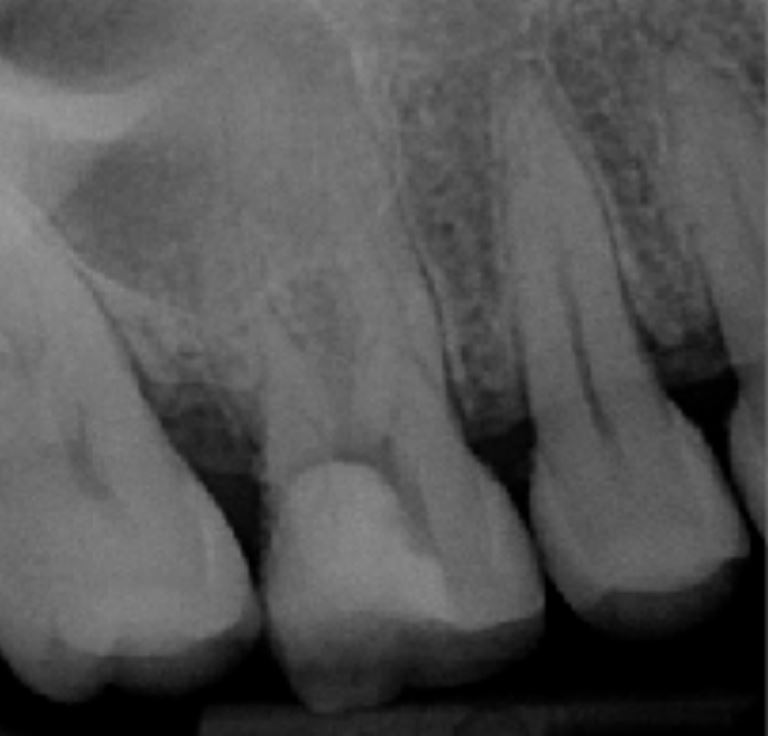

Radio pré-opératoire

Première molaire 16 présentant une image radio-claire au regard des racines mésiales et palatines

Test de vitalité négatif

Pansement en place et dent ouverte en urgence en milieu hospitalier